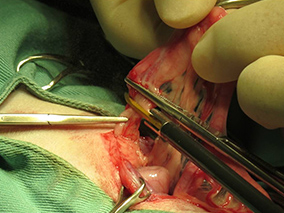

この子は肝臓の数値が高かったため、肝臓の観察と生検を避妊手術と同時に実施しました。

手術後の傷口です。肝臓の検査をしても避妊手術の傷跡と変わりません。

手術後も回復が早く、元気に退院していきました。